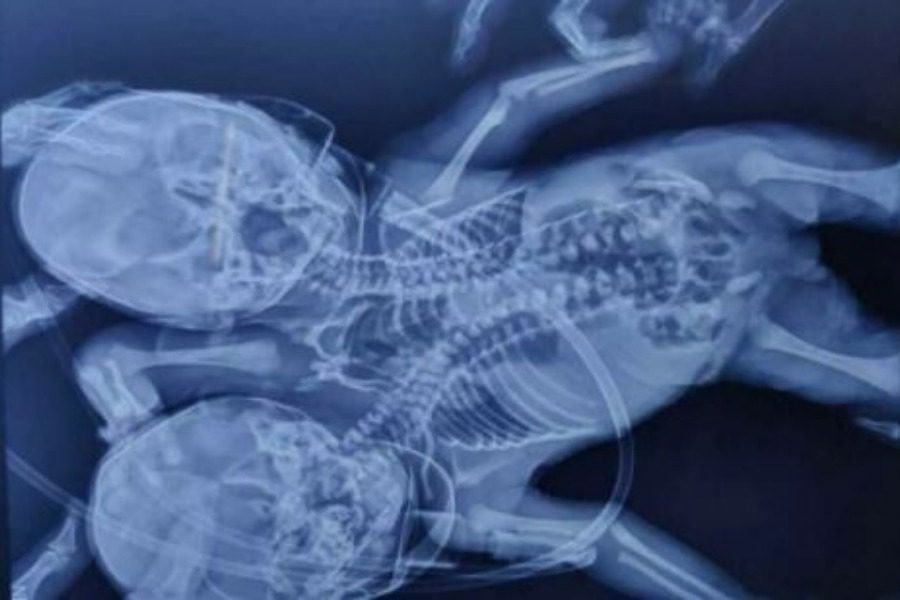

Γεννήθηκε μωρό με δύο κεφάλια, τρία χέρια και δύο καρδιές

Έκπληκτοι έμειναν γιατροί στην Ινδία, όπου όπου ένα μωρό γεννήθηκε με δύο κεφάλια, τρία χέρια και δύο καρδιές.

Σύμφωνα με τους γιατρούς, αυτή η διαταραχή είναι γνωστή ως δικέφαλος parapagus dicefalik όπου δύο μωρά ενώνονται με έναν κορμό που συχνά οδηγεί σε θνησιγένεια.